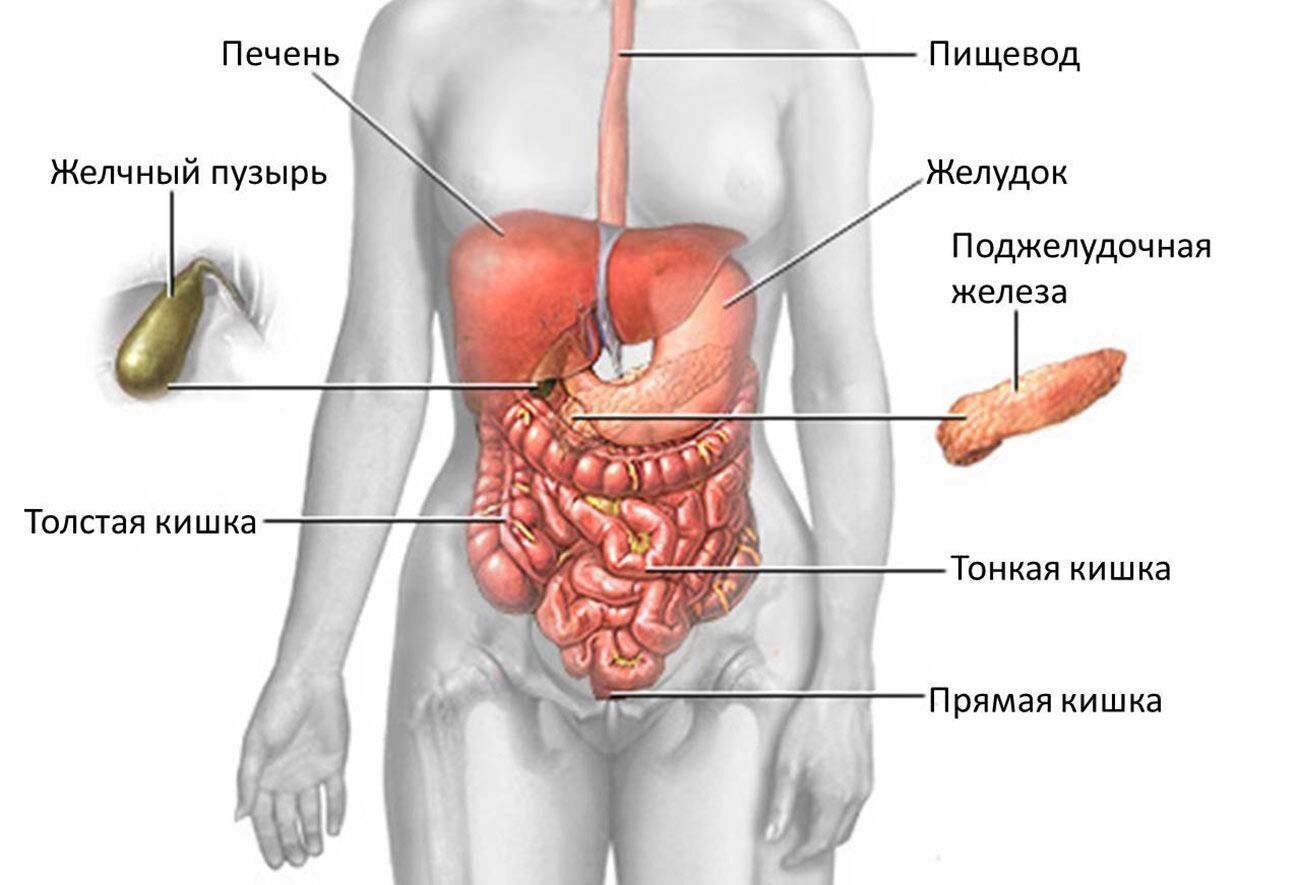

Анатомия желудка и сердца: визуализация и изучение

Раздел: Фотопанорама